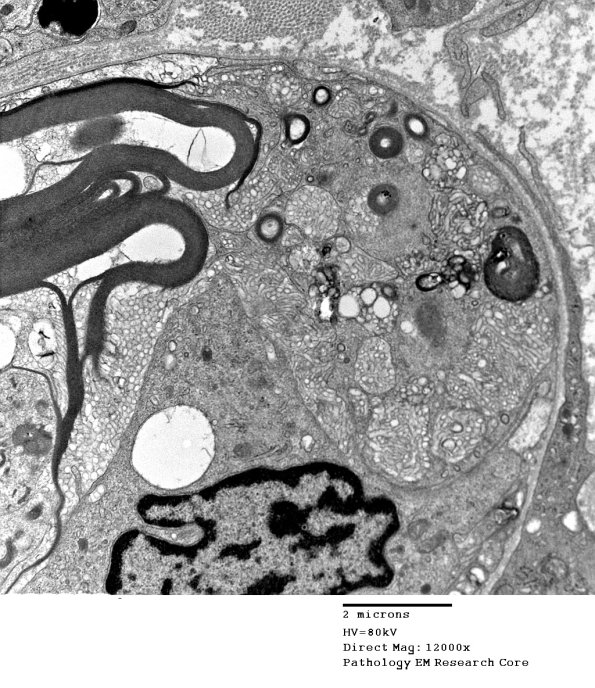

1D1C,D Higher magnification of the remaining myelin sheath and the axon (arrow, 1D1D) which is surrounded by macrophage processes. Notice that the myelin is undergoing vesicular demyelination which represents clear degenerative change in this case as opposed to the artifact we often see resulting from delayed fixation. (electron micrographs)